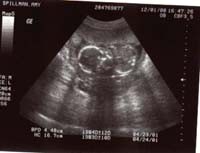

Cody's pics